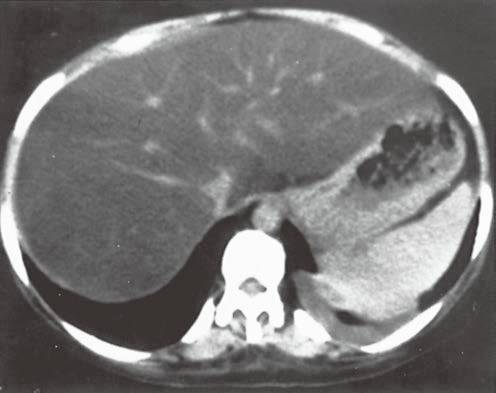

| 类 型 | 影像表现 | 小 结 |

| 肝淤血(图6) | 肝脏体积增大伴弥漫性密度减低。 | 见于充血性心力衰竭或缩窄性心包炎。尽管中心静脉压升高而导致下腔静脉和肝静脉明显扩张(不同于布加综合征,肝静脉和变细的下腔静脉不显影),但强化形式与布加综合征相似。 |

图6充血性心力衰竭